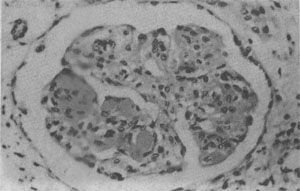

(1)肾:肾功能衰竭是SLE的主要死亡原因。SLE病人几乎均有不同程度的肾损害,约60%病便以狼疮性肾炎为主要表现.常见的类型有系膜增生型(10%~15%)、局灶增生型(10%~15%)、弥漫增生型(40%~50%)和膜型(10%~20%)。各型狼疮性肾炎的病变,类同于相应的原发性肾小球肾炎,各型病变间常有交叉,因此肾小球的病变呈多样性,晚期可出现典型的硬化性肾炎的表现。肾炎病变的发生主要基于肾小球中免疫复合物的沉积,可位于系膜区、内皮下和上皮下。其中弥漫增生型狼疮性肾炎中内皮下大量免疫复合物的沉积,是SLE急性期的特征性病变。在弥漫增生型及膜型病例中,约半数病例在间质及肾小管基膜上亦有免疫复合物沉积,因此肾小球病变和间质的炎症反应在狼疮性肾炎中十分明显(图4-10)。苏木素小体的出现有明确的诊断意义。

狼疮性肾小球肾炎

图4-10 狼疮性肾小球肾炎

肾小球毛细血管丛节段性纤维素样坏死,伴系膜细胞增生;间质炎细胞浸润